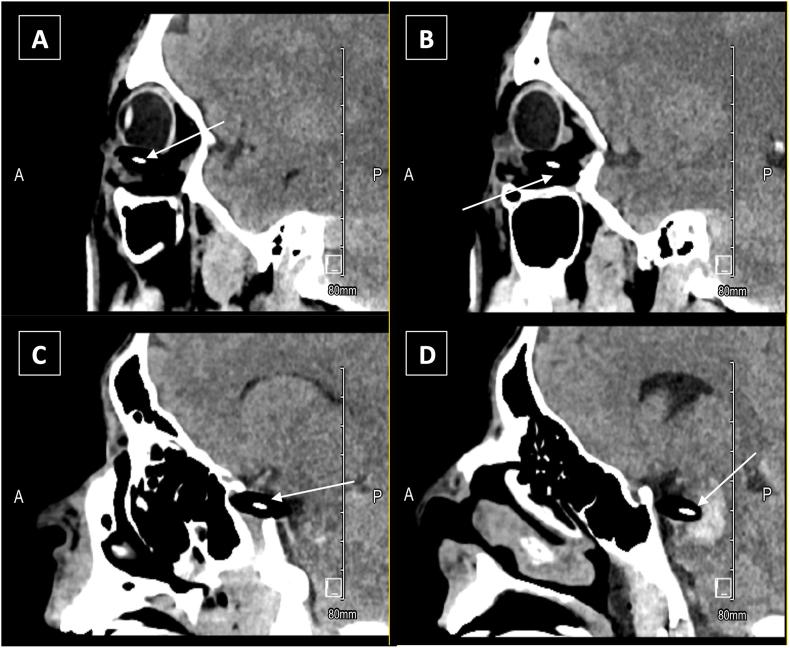

A 21-year-old Hispanic male presented urgently to the emergency department (ED) after self-inflicted ocular trauma with a wood-cased pencil, which was embedded in the upper eyelid and transversed the left orbit, extending to the pons, as depicted on computed tomography (CT). Physical examination of the left eye was difficult due to the risk of displacement of the pencil within the brainstem and concern for further damage. The pencil was successfully removed via fluoroscopy-guided neuro-interventional catheterization and stenting. Following the removal of the foreign body, there was no apparent damage to the globe, and a canthotomy/cantholysis was performed due to increased retro-orbital pressure. The neurovascular damage sustained by the trauma led to a progressive neurological decline in the following days and, ultimately, a fatal outcome.

一名21岁的西班牙裔男性在使用木质铅笔自我造成眼部外伤后紧急前往急诊科(ED),计算机断层扫描(CT)显示铅笔嵌入上眼睑并横穿左眼眼眶,延伸至脑桥。由于铅笔在脑干内移位的风险以及担心进一步损伤,对左眼进行体格检查很困难。通过荧光透视引导的神经介入导管插入术和支架置入术成功取出了铅笔。取出异物后,眼球没有明显损伤,由于眶后压力增加,进行了眦切开术/眦松解术。外伤造成的神经血管损伤在接下来的几天导致神经系统逐渐衰退,最终导致死亡。